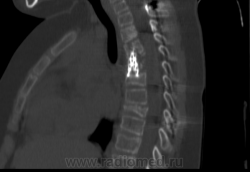

Пол пациента: Женский пол Тип патологии: Другое Область исследования: Скелетно-мышечная система Методы исследования: КТ Был проведен КТ- контроль грудного отдела позвоночника. http://www.radiomed.ru/cases/gistiocitoz https://radiomed.ru/sites/default/files/styles/case_slider_image/public/user/117/_130048573002_0003.png?itok=CfqBj1dp https://radiomed.ru/sites/default/files/styles/case_slider_image/public/user/117/_130048573002_0004.png?itok=caNezyWr https://radiomed.ru/sites/default/files/styles/case_slider_image/public/user/117/_130048573002_0005.png?itok=3g-aX0h9 ID:3039 Пт, 16/04/2010 - 21:55 #1 Almo Не на сайте Был на сайте: 1 день 5 часов назад Зарегистрирован: 28.09.2008 - 18:50 Публикации: 8281 Виталий, мало клинических данных( преамбулы). Пт, 16/04/2010 - 22:04 #2 Almo Не на сайте Был на сайте: 1 день 5 часов назад Зарегистрирован: 28.09.2008 - 18:50 Публикации: 8281 Извините, невнимательно прочёл заголовок!